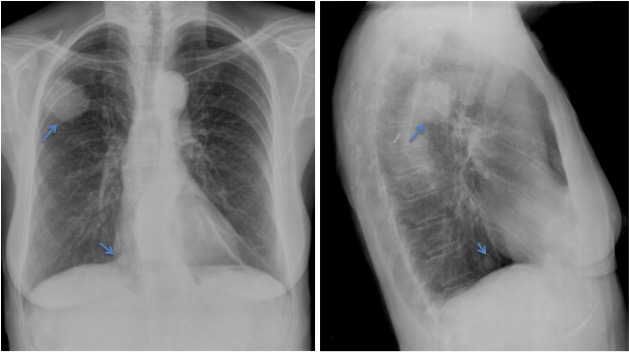

CASO: sospecha de neumonía.

Hallazgos:

- En un principio podríamos decir que existe un aumento de densidad retrocardiaco que podría ser compatible con condensación neumónica a dicho nivel, sin embargo estamos ante una placa poco inspirada, lo cual puede llevarnos a cometer errores diagnósticos.

- Se recomendó volver a realizar la radiografía, observar a continuación:

Ya no se observa el aumento de densidad retrocardiaco, la placa es normal.

INSPIRACIÓN: Una placa bien inspirada es aquella en la que se observar 6-7 arcos costales anteriores o 10-11 arcos costales posteriores. Lo contrario puede producir imágenes falsas de condensaciones o de seudocardiomegalia.